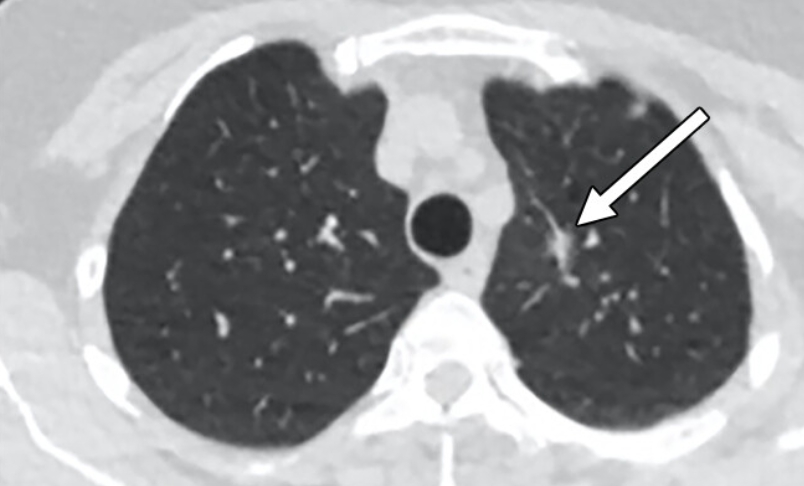

Q8. 흉부CT 결과에서 ‘폐결절’이 나왔다는 말은 뭔가요?

A. 흉부ct로 볼수있는 질환 폐결절은 말 그대로 폐 안에 작은 혹이 있다는 뜻입니다. 대부분 양성(암이 아님)이고, 오래된 염증이나 석회화에 의한 것일 수도 있습니다. 그러나 결절의 크기가 8mm 이상이거나, 형태가 불규칙한 경우에는 추가 검사가 필요합니다. 영상의학과에서는 결절의 밀도, 경계, 주변 변화 등을 세밀하게 분석해 암 가능성을 판단합니다.